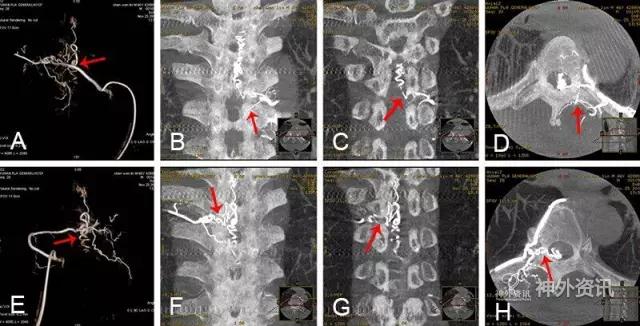

脊髓血管造影,尤其是经皮穿刺股动脉选择性脊髓血管造影,是诊断脊髓血管疾病的金标准。至今,由于影像技术、DSA血管造影机诸多后处理功能的进步,如三维成像技术(three-dimensional imaging technology;图1)、最大密度投影成像(maximum intensity projection,MIP;图2)、双容积重建(double volume,DV;图3)与三维影像融合技术(three dimensional image fusion technology;图4)及我们研究开发的三种技术的动态成像技术(dynamic image fusion technology),可以给出冠状位从前到后再从后到前、矢状位从左到右再从右到左、轴位从上到下再从下到上的全方位多角度动态立体解剖影像(图5),就更提高了对脊髓血管疾病诊断的认识和治疗水平。因此,应该说这些三维融合影像才是脊髓血管疾病诊断的金标准[1,2]。

图2: 两侧T10供血硬脊膜动静脉瘘(SDAVF) ,↑示瘘口。A.3D-DSA;B~D.最大密度投影(MIP)冠状位、矢状位和轴位融合影像;E.3D-DSA;F~H.MIP冠状位、矢状位和轴位融合影像。